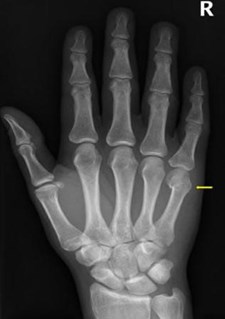

U heeft een breuk in het vijfde middenhandsbeentje (metacarpala 5). De breuk zit in de buurt van de knokkel van uw pink. We behandelen deze breuk met tape en drukverband. We maken geen standaard poliklinische controle afspraak, deze is over het algemeen niet nodig. Het is belangrijk uw vinger te bewegen zodra dit kan, om stijfheid te voorkomen.

Een gebroken middenhandsbeentje komt vaak voor. We behandelen u met tape, ook wel buddy tape genoemd, of er wordt een buddy loop gemaakt van klittenband. Daarnaast krijgt u drukverband om de breuk te ondersteunen. Zo heeft u minder pijn en geneest de breuk het snelst.